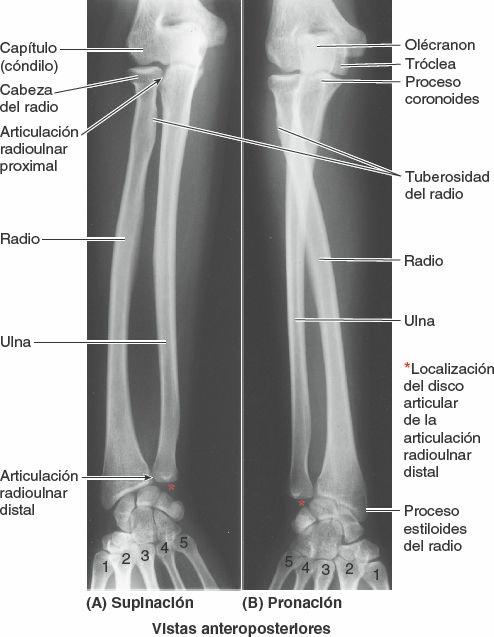

Movimientos

Durante la pronación y la supinación del antebrazo, la cabeza del radio rota dentro del anillo formado por el ligamento anular y la incisura radial de la ulna. La supinación gira la palma anteriormente, o superiormente si el antebrazo se encuentra en flexión (figs. 3-103, 3-105 Y 3-106). La pronación gira la palma posteriormente, o inferiormente si el antebrazo se encuentra en flexión. El eje de estos movimientos pasa proximalmente a través del centro de la cabeza del radio, y distalmente a través del lugar de inserción del vértice del disco articular en la cabeza (proceso estiloides) de la ulna. Durante la pronación y la supinación es el radio el que rota: su cabeza rota dentro del anillo en forma de copa formado por el ligamento anular y la incisura radial de la ulna. Distalmente, el extremo del radio rota alrededor de la cabeza de la ulna. Casi siempre la supinación y la pronación se acompañan de movimientos sinérgicos de las articulaciones del hombro y el codo que producen movimientos simultáneos de la ulna, excepto cuando el codo se encuentra en flexión.

Articulación radioulnar distal

La articulación radioulnar distal (inferior) es una articulación sinovial de tipo trocoide (fig. 3-104). En ella, el radio se mueve alrededor del extremo distal de la ulna, relativamente fijo.

Superficies articulares

La cabeza redondeada de la ulna se articula con la incisura ulnar de la cara medial del extremo distal del radio. Un disco articular de la articulación radioulnar distal, fibrocartilaginoso y de forma triangular (por ello denominado en ocasiones ligamento triangular por los clínicos), une los extremos de la ulna y el radio y es la principal estructura estabilizadora de la articulación (figs. 3-104, 3-105 y 3-107 B). La base del disco articular se inserta en el borde medial de la incisura ulnar del radio, y su vértice lo hace en la cara lateral de la base del proceso estiloides de la ulna. La superficie proximal de este disco se articula con la cara distal de la cabeza de la ulna. Por ello, en una sección coronal, la cavidad articular tiene forma de L con su barra vertical entre el radio y la ulna, y la horizontal entre la ulna y el disco articular (figs. 3-107 B y C, y 3-108 A). El disco articular separa la cavidad de la articulación radioulnar distal de la cavidad de la articulación radiocarpiana.

Durante la pronación del antebrazo y la mano, el extremo distal del radio se desplaza (rota) anterior y medialmente, para cruzar por delante de la ulna (figs. 3-103, 3-105 Y 3-106). Durante la supinación, el radio deja de cruzarse con la ulna, ya que su extremo distal se desplaza (rota) lateral y posteriormente, y los huesos se vuelven paralelos.